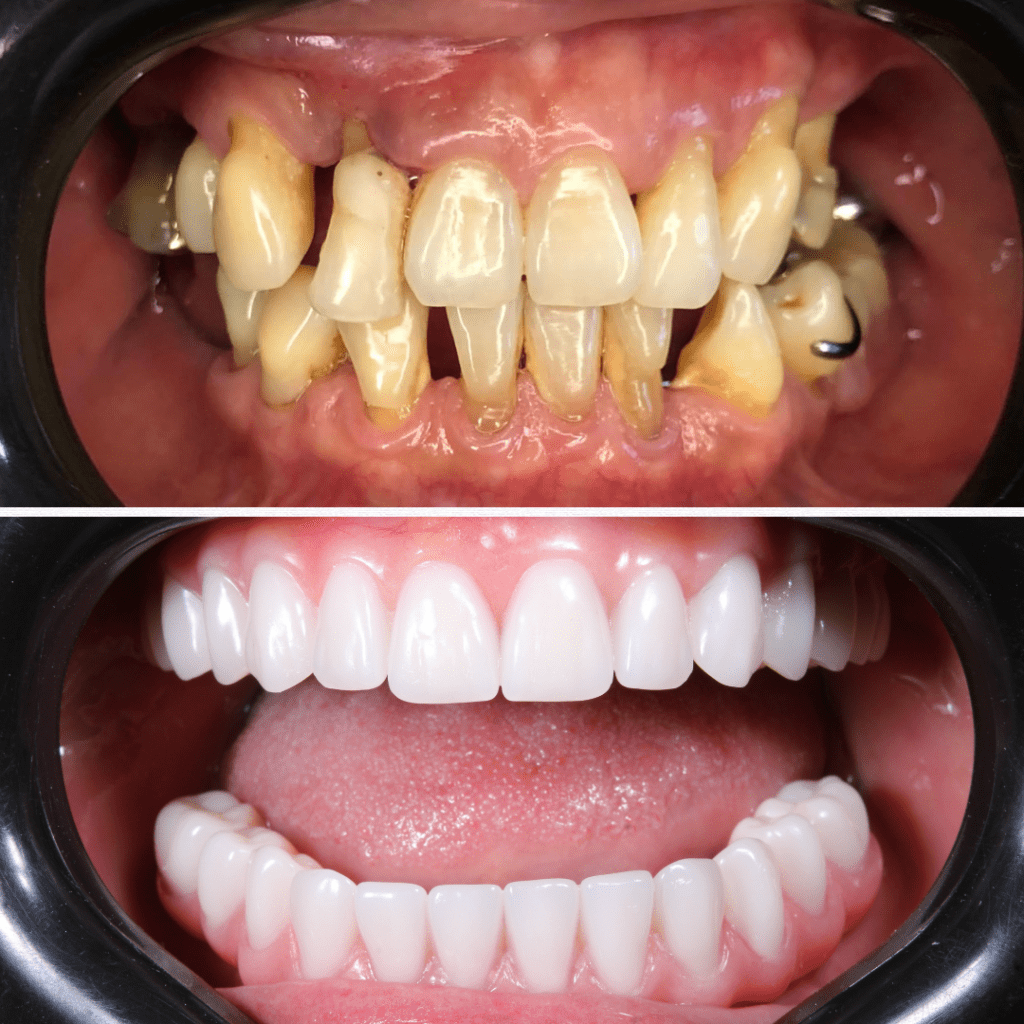

Os dentes vizinhos permanecem íntegros

Os dentes vizinhos permanecem íntegros